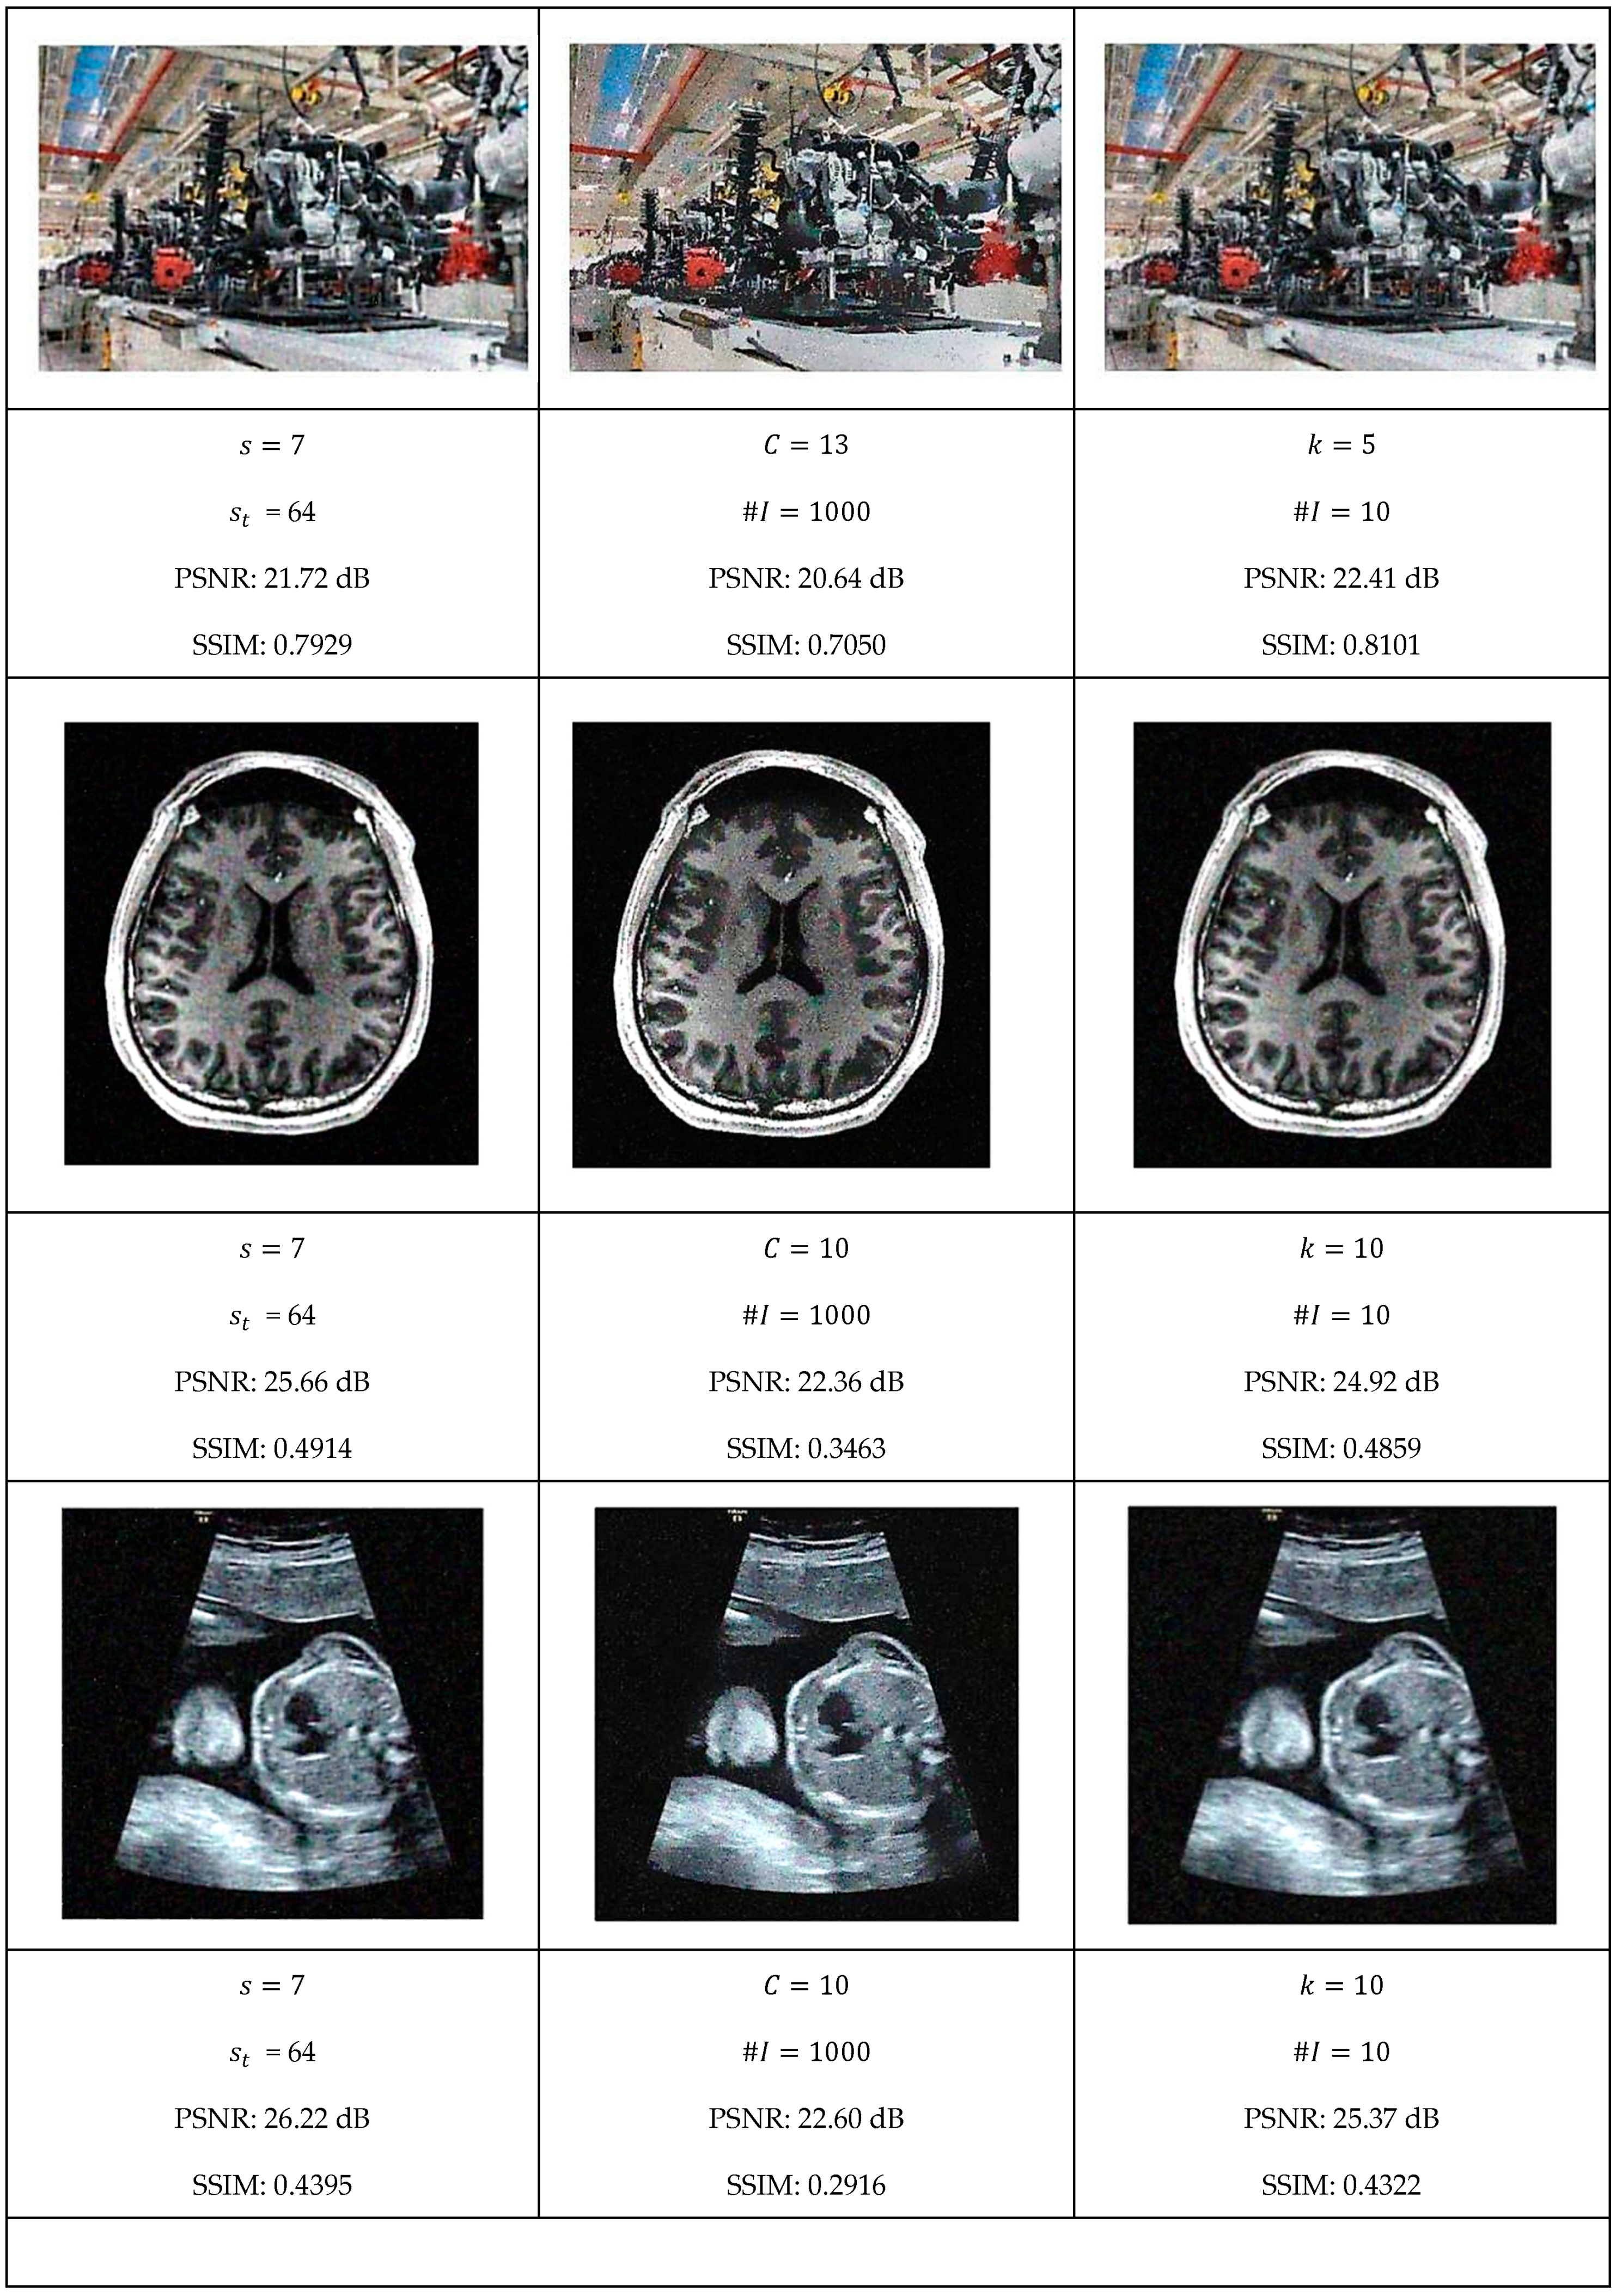

This section presents a comprehensive comparative analysis of our geodesic filtering approach against the state-of-the-art methods. The key to this comparison is based on PSNR and SSIM difference metrics. The noisy images shown in Figure 8 were processed using various implementations of the filtering algorithms described in Section 2. To be fair in our comparison, as with the geodesic filter, we tuned the parameters to produce the best PSNR value possible. The results of this comparison are collected in Figure 9 and Figure 10.

Each algorithm was carefully tuned to achieve optimal performance using the same test image database with standardized noise conditions. For each filter, the tuning parameters are as follows:

• Least Median Filter: window size s and tile size s t ;

• Gradient Anisotropic Diffusion: conductance C and number of iterations #I;

• Curvature Anisotropic Diffusion: the mean curvature of the level sets k and number of iterations #I;

• Bilateral Filter: s kernel size, σ d spatial distance weight, and σ c color distance weight;

• Gaussian Weighted Wavelet DIP Neural Network: σ w Gaussian variance, ϵ minimum tile loss, s t tile size, and s o tile overlap size.

In summary, the quantitative evaluation presented in Table 1 and Table 2 confirms that geodesic filtering provides dual performance advantages: achieving noise reduction metrics (PSNR) comparable to state-of-the-art alternatives while significantly outperforming them in structural preservation (SSIM). This superiority in preserving image structure is evident across the entire image dataset, with particularly notable advantages in regions containing intricate textures and fine details that traditional methods frequently over-smooth or distort.

The results clearly demonstrate that while other filtering approaches may achieve similar noise reduction performance, they do so at the cost of structural integrity. Geodesic filtering, in contrast, maintains the delicate balance between noise suppression and feature preservation, making it particularly valuable for applications where preserving the semantic content of images is paramount.